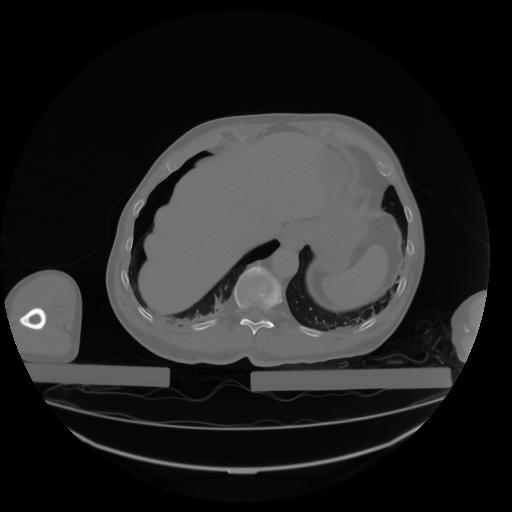

27 CUERPO,CE,Axial,3.0,CUERPO,,